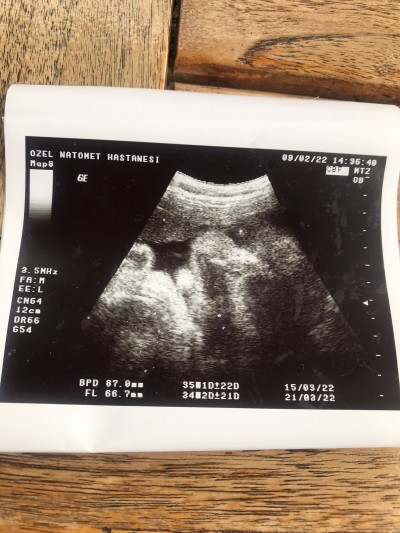

Geldiğimden beri fotoğrafına bakıyorum keşke hemen doğsa artık günler sanki ilerlemeyi bıraktı. Doktor sezeryan istersen 38de alırız dedi geceleri çok sancım olduğundan. Erkek bebişler biraz daha geç doğabiliyor sanırım...